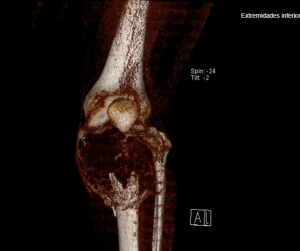

🏥 Cirugía Oncológica en Paciente Pediátrico en el HMyN Read More »